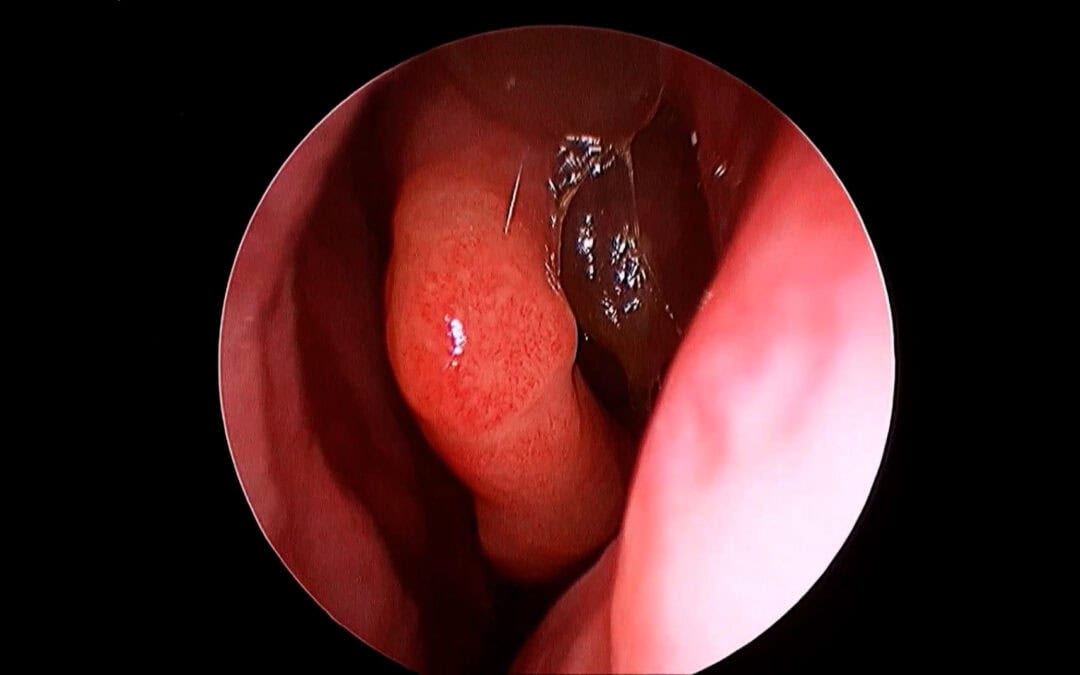

Septal Swell Body The Overlooked Cause of Nasal Obstruction

The Septal Swell Body: The Missing Target in Nasal Obstruction Surgery Despite decades of refinement in nasal airway surgery, one structure continues to be consistently overlooked: the septal swell body (SSB). While inferior turbinate reduction and septoplasty...